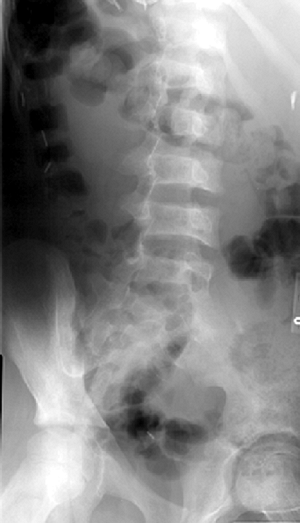

radiography include osteopenia, biconcave vertebrae, and medullary

expansion and cortical thinning due to marrow hyperplasia (47) (Fig. 11.2). Vertebral collapse has been reported in two children (48). Osteopenia, although rarely a clinical problem (49,50), can be detected by calcaneal ultrasound and serum markers of bone turnover (51). Multifocal

Figure 11.2 Oblique radiograph of the spine in a patient with sickle cell disease. Note biconcave vertebral bodies.